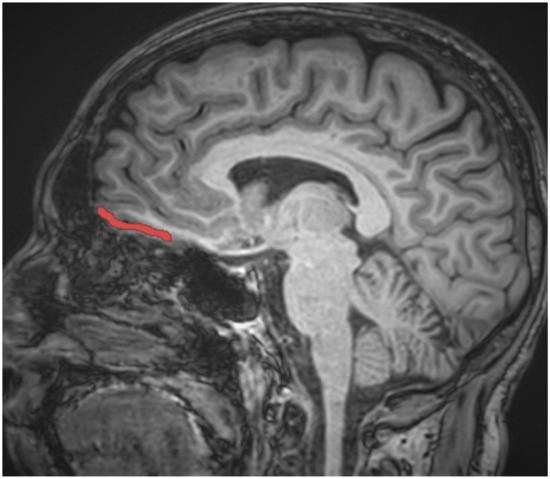

Image analyses were carried out using the FreeSurfer program (version 4.4), a free program to use and available to download online, which was used to reconstruct the cortical surfaces and detect the cortical thickness from magnetic resonance images (http://surfer.nmr.mgh.harvard.edu, accessed on 10 November 2022). For all processes, the method of Epstein et al. was followed [39]. The process utilised to analyse each subject’s brain images is available on the FreeSurfer website. Scans were processed by a radiologist who was blind to both the diagnosis of patients with alcohol use disorder and to whom was a patient or a healthy control subject. The process included motion correction, extraction of the brain tissue, transformation to Talairach space, segmentation and parcellation into the OFC region as described by Desikan et al. [40]. After this process, scans were also examined by a senior radiologist (M.K.) to ensure that segmentation and parcellation were performed correctly. In addition, scans were also reviewed for the presence of any artifact. However, no artifact was found. Uncorrected OFC cortical volumes (mm3) were divided by the total segmented brain volume (mm3) and then multiplied by 1000, to obtain the corrected cortical volumes. In contrast to Epstein et al.’s study, the OFC region was investigated in two parts, as left and right OFC [39]. Assistance was obtained from standard neuroanatomy atlases during all measurements [41,42,43]. On the other hand, the boundaries of the OFC region were adapted from Portas et al. and Riffkin et al. [44,45]. By using those guidelines, the same procedure as in our previous studies was preferred [46,47]. When determining the volumes of the OFC, the superior boundary of the OFC was defined by a line extending from the anterior commissure to the posterior commissure. The point at which the olfactory sulcus first appeared was determined as the posterior landmark. As expected, while the inferior boundary of the OFC was selected the most inferior aspect of the cortex, the most lateral edge of the brain cortex was also accepted as the lateral boundary of OFC. Finally, the longitudinal fissure was accepted as the medial boundary of the OFC. Sample imaging owing to the OFC is presented in Figure 1, whereas the images obtaining from the Freesurfer program are presented in Figure 2.

Figure 2.

Sample cortical thickness measure for the OFC.